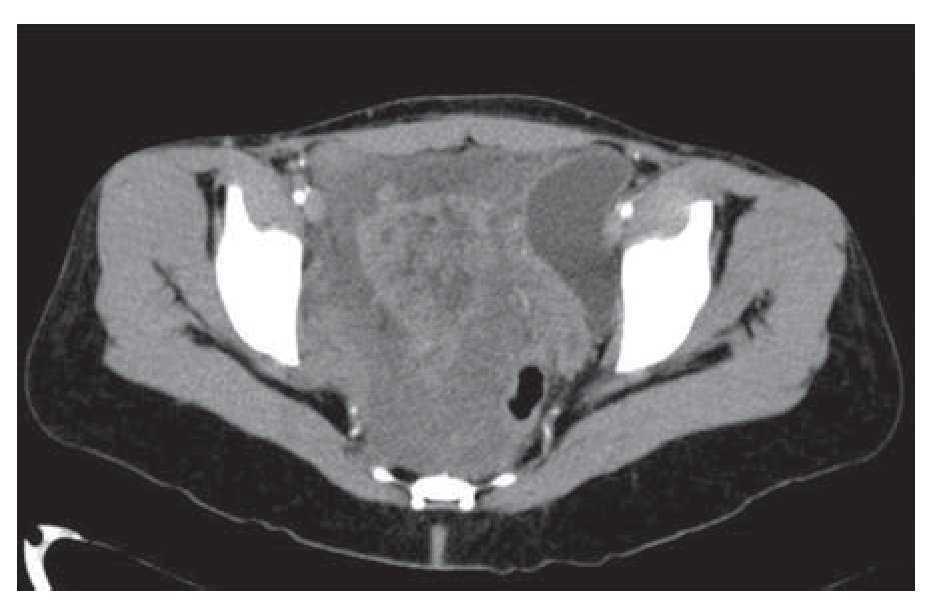

Mujer de 41 años de edad, sin antecedentes, que consultó por historia de dolor pélvico difuso, de baja intensidad, no irradiado, de ocho meses de evolución. Al examen físico se encontró una masa adherida a planos profundos y poco dolorosa a la palpación. Se le realizó una tomografía computadorizada que informó una extensa neoplasia pélvica de características malignas, que se extendía hasta el espacio isquiorectal, con desplazamiento y compresión de la vejiga y el útero, además de escaso líquido alrededor de la lesión (Figura 1). Se realizó una resonancia magnética nuclear que demostró una lesión de 14 x 14 cm, posiblemente de origen lipomatoso con degeneración mixoideangiolipomatosa, con probable infiltración al recto y sigmoides, dilatación pielo-ureteral bilateral por obstrucción del tercio distal de los uréteres (Figuras 2 y 3). Se realizó una colonoscopia que sólo evidenció desplazamiento del sigmoides por compresión extrínseca. Se le realizó una laparotomía exploratoria encontrando una masa pélvica de 15 x 20 cm, la cual se pudo separar de las estructuras adyacentes y resecar en su totalidad. El reporte histopatológico fue de una masa de 15 x 18 cm, con un peso de 260 g, de color amarillo-gris liso y opaco, de aspecto nodular y consistencia blanda. Al corte se encontraron áreas quísticas compatibles con angiomixoma (Figura 4). La paciente presentó una evolución satisfactoria, se le dio egreso. Actualmente se encuentra asintomática y sin datos de recurrencia.

Figura 1. Tomografía computadorizada que mostró masa de características malignas, desplazando y comprimiendo la vejiga y útero